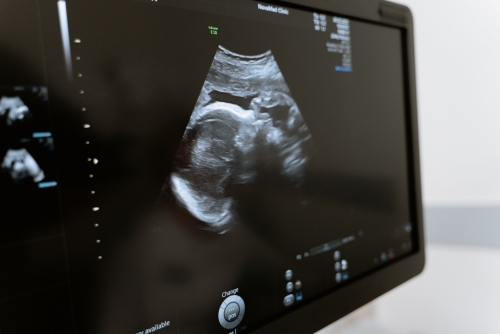

常規(guī)超聲檢查指的是二維超聲檢查,二維超聲檢查即二維超聲檢查,小排畸是為了更好地觀察胎兒生長發(fā)育情況,排除畸形的檢查。小排畸檢查能夠排除絕大多數(shù)胎兒畸形,如先天性心臟病、唇腭裂、水腫胎,以及多指畸形、重度腦膨出等。

1、先天性心臟病:可通過二維超聲檢查直接觀察心臟及大血管的形態(tài)、結(jié)構(gòu)、連續(xù)性及血流改變,二維超聲檢查比較直觀,能夠顯示出心臟的三維圖像,所以在懷孕期間需要定期做產(chǎn)檢,一般在懷孕20-26周需要做四維彩超大排畸檢查,判斷胎兒是否有畸形;

2、唇腭裂:二維超聲檢查能夠比較清晰地顯示出胎兒嘴唇及面部發(fā)育情況,而且還能夠觀察到是否存在唇腭裂的情況,所以在懷孕期間需要常規(guī)做三維彩超檢查,判斷胎兒是否存在唇腭裂;

超聲檢測2

3、水腫胎:如果孕婦出現(xiàn)水腫胎,也需要做二維超聲檢查,判斷胎兒是否存在水腫胎,因為如果孕婦出現(xiàn)水腫胎,大多是由于妊娠期高血壓導(dǎo)致,所以在懷孕期間要定期做產(chǎn)檢,隨時觀察水腫胎的情況;

4、多指畸形:產(chǎn)前二維超聲檢查可以觀察到胎兒手指、腳趾等外觀畸形,如果出現(xiàn)多指畸形,還需要做三維超聲檢查,判斷是否有多指畸形的情況;

5、重度腦膨出:二維超聲檢查能夠比較清晰地觀察胎兒腦組織、脊柱、羊水等情況,如果出現(xiàn)重度腦膨出,也需要做三維超聲檢查判斷是否有腦積水。

孕期需要做好定期產(chǎn)檢,建議在懷孕24-26周需要到醫(yī)院做四維彩超大排畸檢查,判斷胎兒是否有畸形,如果出現(xiàn)比較嚴(yán)重的畸形,建議在醫(yī)生指導(dǎo)下終止妊娠。